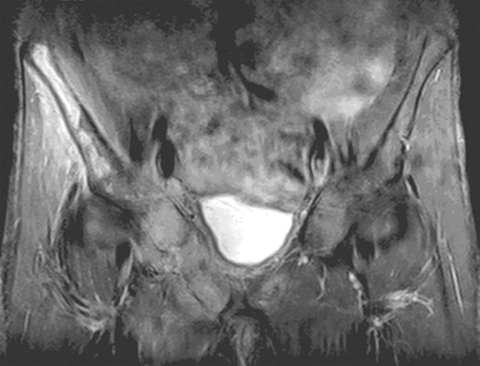

MRI helped in making the diagnosis and delineating the extent of the muscle involvement in all patients, as (see Box 2) the high signal intensity of the pathological process (prolonged T2) can be easily distinguished from the relatively low signal intensity of normal muscle (shortened T2). The superiority of MRI for differentiating pyomyositis from other pathological processes, outlining the extent of involvement and localising fluid collections, has been previously reported.8 The ability of MRI to obtain multiplanar contiguous sections provides excellent anatomical detail of each muscle group and precisely locates the site of disease. MRI scans in 43 cases of pyomyositis found that hyperintense signals on T2-weighted images were detected in all patients.18 A hyperintense rim on unenhanced T1-weighted images and peripheral enhancement after gadolinium injection was useful for identifying the number, size and location of soft tissue abscesses.18